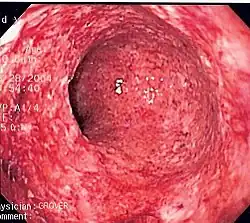

Chronisch-entzündliche Darmerkrankungen

Zu den chronisch-entzündlichen Darmerkrankungen werden üblicherweise Morbus Crohn und Colitis ulcerosa gezählt, die in Deutschland mit jeweils 5–6 Neuerkrankungen pro 100.000 Einwohner pro Jahr etwa gleich häufig auftreten. Kennzeichnend ist eine dauerhafte (chronische) Immunreaktion in der Darmwand, die in Schüben auftritt. Bei beiden Erkrankungen sind die Auslöser und Mechanismen der Krankheitsentstehung noch unklar.[38] Franz Alexander zählte sie 1950 zu den sieben psychosomatischen Krankheiten, den „Holy Seven“, diese These gilt inzwischen als überholt. Mittlerweile wurden auch genetische Faktoren identifiziert, die bei der Entstehung der Krankheiten eine Rolle spielen könnten. Morbus Crohn und Colitis ulcerosa unterscheiden sich hinsichtlich des Krankheitsverlaufs und ihres Erscheinungsbildes (Morphologie).

Der Morbus Crohn ist die Entzündung der ganzen Darmwand mit allen Schichten, weshalb es häufig zu Fisteln (beispielsweise Analfisteln) kommt. Grundsätzlich kann der gesamte Verdauungstrakt befallen sein, typischerweise betrifft die Entzündung aber den Endabschnitt des Dünndarms (Ileum) und den Dickdarm. Die Entzündung breitet sich nicht kontinuierlich vom Entstehungsort aus, sondern „springt“ von Abschnitt zu Abschnitt.[39] Der Morbus Crohn heilt häufig nur unvollständig ab und ist durch eine hohe Rezidiv-Rate, also wiederkehrende Entzündungen, gekennzeichnet.[40]

Bei der Colitis ulcerosa beschränkt sich die Entzündung dagegen auf die Schleimhaut. In der Regel beginnt die Entzündung akut im Rektum und breitet sich von dort kontinuierlich auf die restlichen Dickdarmabschnitte aus. Ist der ganze Dickdarm befallen, ist von einer Pancolitis die Rede. Bei etwa 10 bis 20 % der Pancolitiden kommt es zur sogenannten „Backwash-Ileitis“, bei der die Entzündung auf das Ileum des Dünndarms übergreift.[41] Auch die Colitis ulcerosa verläuft rezidivierend, also mit wiederkehrenden Schüben. Zwischen den Schüben heilt der Darm in der Regel aber vollständig ab.[42] Beim akut fulminanten Verlauf ist das toxische Megacolon eine seltene, aber lebensbedrohliche Komplikation mit der Gefahr einer eitrigen Bauchfellentzündung. Colitis ulcerosa erhöht das Risiko, an Darmkrebs zu erkranken.[43] Durch eine Kolektomie, Entfernung des Dickdarms, ist Colitis Ulcerosa theoretisch heilbar,[44] es wird dann hierfür ein Stoma bzw. ein Pouch erstellt.